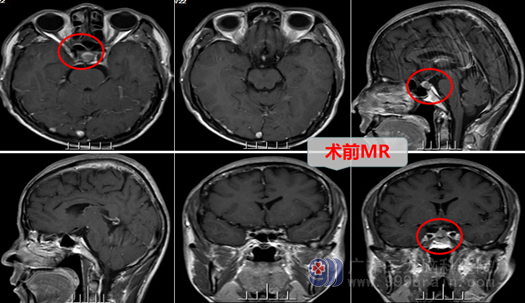

原来,廖先生因为头痛头晕的症状到广东三九脑科医院做检查被诊断为颅内鞍区占位:rathkes’囊肿,原因是脑袋里长了病变作祟。他被收治到神经内镜治疗有特色的神经外十科。

医生告诉廖先生,颅脑鞍区靠近头颅的中心和颅底正中偏前的位置,其对应颅底外的投影是蝶窦。而鼻腔和鼻窦相通,是人体本身就具有的腔隙,可以变成通向颅底病变的手术通道和空间,由于现代内镜技术的发展,现在很多神经外科手术可以利用这些空间作为很好的手术入路。内镜经鼻蝶鞍区占位切除术是脑科医院外十科经常采用的针对鞍区及其他中线颅底占位病变切除的微创手术方式,利用只有4毫米左右粗的神经内镜进入鼻腔,进去以后,根据解剖结构(或加上神经影像导航)找到鞍底,磨开鞍底,切开硬膜,即可到达鞍区囊肿的位置,主刀医生再在内镜下将其切除掉。传统的开颅手术治疗鞍区占位的方法,要在额颞部切开头皮,锯下骨瓣,切口大,风险高,对患者的创伤大,患者需要的康复时间长,而且头部肯定会遗留永久可以看到的手术疤痕。而内镜经鼻蝶鞍区占位病变切除术,作为微创方法与其对比,出血少,痛苦小,风险更低,对患者的创伤小,术后康复更快,尤其是爱美的人士,头部表面确实没有手术疤痕。

于是乎,兴奋的廖先生在完善了相关检查与术前准备以后,接受了外十科团队为他行“内镜下经鼻蝶鞍区占位病变切除术”,手术很顺利,病变被切除了,术后的廖先生精神良好,没有明显的不适,现在头上看不到手术疤痕的廖先生已经开开心心康复出院了。他说:其他人还以为他没做手术吶?。